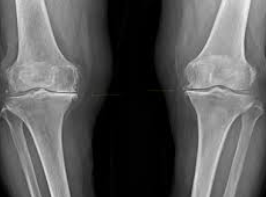

퇴행성 관절염, 일명 '골관절염'은 관절을 보호하는 연골이 닳아 없어지면서 발생하는 질환입니다. 이로 인해 관절의 뼈가 서로 마찰을 일으키며 통증, 부기, 그리고 운동 범위의 제한을 초래합니다. 퇴행성 관절염은 주로 노화와 관련이 있으며, 무릎, 엉덩이, 손, 그리고 척추와 같은 관절에 자주 나타납니다.

증상은 점진적으로 발전하며, 초기에는 운동 후 통증이 나타나기 시작합니다. 시간이 지남에 따라 휴식을 취해도 통증이 지속되며, 관절의 경직과 부기가 동반됩니다. 심한 경우에는 관절의 변형까지 발생할 수 있습니다. 날씨가 추울 때나 습할 때 통증이 더 심해지는 것을 경험할 수도 있습니다.